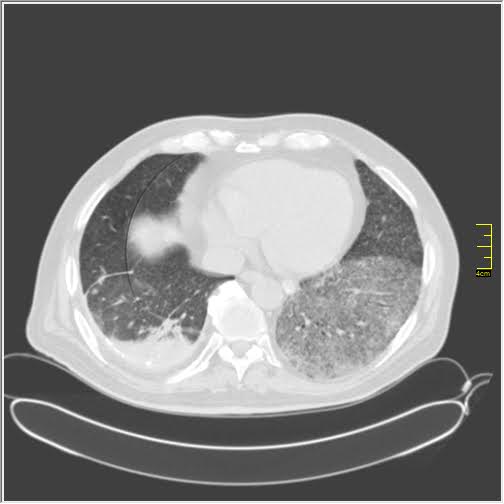

Pacijent sa malignim oboljenjem i kovidom-19. Obostrano bazalno.

Kardiološki pacijent sa kovidom-19

Stanje nakon kovida-19.

Ovo je stanje nakon kovida-19, nimalo dobar nalaz.